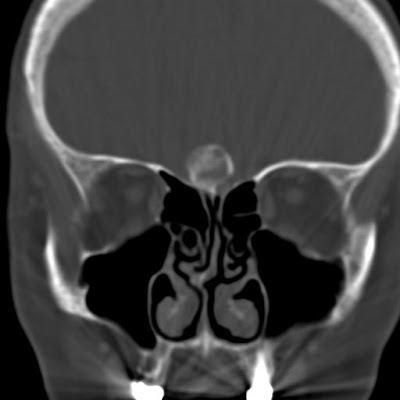

Bal oldali véres orrváladékozás miatt kérték arckoponya CT-vizsgálatát, mely a melléküregekben kórosat nem talált. A lamina cribrosán ülő, olfactorius meningeomára jellemző elhelyezkedésű, középvonali meszes, kerek képlet látszik.